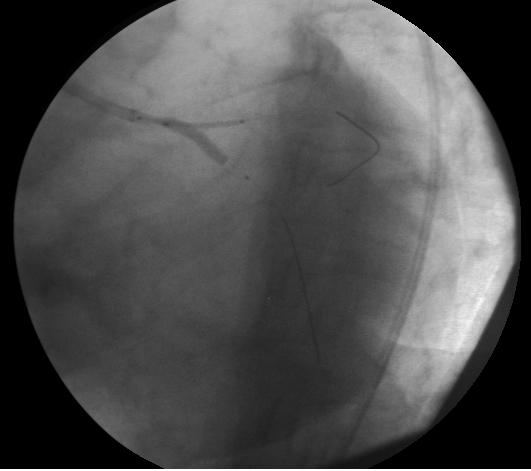

600 mg Clopidogrel, 300 mg Aspirin, Atorvastatin 40 mg, and Heparin 7500 U were given. A 5 Fr sheath was inserted via the left femoral artery in case an IABP was needed. ACT was checked, and heparin administered to have optimal anticoagulation. LMCA was engaged with a 7Fr EBU4 guiding catheter, and floppy guidewires were inserted into the ramus and LCX that were predilated with a Simpass 2.5x15mm balloon (Figure 5, Figure 6). A 2.5x18mm Nobori stent was placed into the LCX, and a Promus Element 3x20mm stent was placed from the LMCA to the ramus. The Nobori stent was withdrawn 3-4mm into the LMCA and inflated at 12atm (Figure 7). The LCX balloon and guidewire were withdrawn, and the ramus stent was inflated at 12atm to crush the stent in the LMCA (Figure 8). When we tried to rewire the LCX with a floppy guidewire, the guidewire kept going under the stent; and the balloon did not follow into the LCX. The stent in the LMCA was post-dilated with a 4x15mm Turquoise balloon for better wall apposition and easier entry into the LCX. The LCX was rewired, and kissing balloon inflations with Simpass 2.5x15mm and Turquoise 4x15mm balloons, both at 10atm, was performed (Figure 9). After kissing balloon inflations and balloon withdrawal, we realized that the ostial part of the LMCA stent was distorted by the guiding catheter (Figure 10). We lost the LCX guidewire position and withdrew the floppy guidwire into the LCX. In order to correct the ostial part of the stent, we inflated a 4.5x15mm Simpass Plus baloon from the LMCA to the ramus at 12atm (Figure 11). Images taken after ballooning showed "orrection"of the stent struts in the LMCA, but the LCX stent showed a new ostial narrowing. Luckily, we rewired the LCX with some difficulty (Figure 12). The LCX ostial struts were postdilated again with a Simpass 2.5x15mm balloon, and the narrowing was corrected (Figure 13, Figure 14).